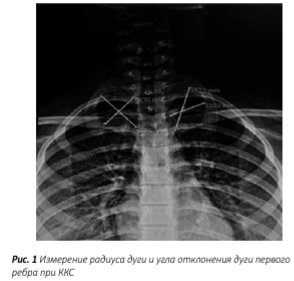

При ККС производился рентгеновский снимок, охватывающий шейные позвонки, ключицу и верхние четыре ребра. На рис. 1 представлено измерение угла отклонения и радиуса дуги первого ребра.

Ориентиром являлась горизонтальная ось ключицы, все расчёты производились по отношению к ней. Расположение первого ребра оценивалось следующим образом: высоким его стояние считалось, когда на прямом рентгеновском снимке выше ключицы проецировались задние части первых трёх, нередко, и четвёртого рёбер. Конфигурация дуги первого ребра оценивалась измерением длины радиуса дуги и угла отклонения дуги по от¬ношению к оси ключицы, т.е. горизонтальной плоскости. В норме дуга первого ребра имеет эллипсоидную форму, и угол отклонения составляет менее 65°, при этом радиус дуги первого ребра длинный. При ККС характерно вертикальное расположение дуги по отношению к оси ключицы, и, за счёт этого, уменьшается длина радиуса дуги первого ребра, а угол отклонения дуги составляет от 60° до 90°.